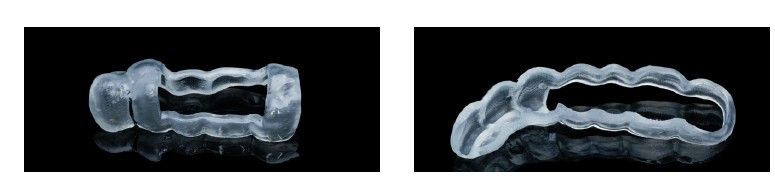

El abordaje del maxilar posterior atrófico con reabsorción ósea en altura y baja densidad es un reto a la hora de ser rehabilitado con implantes dentales. Esto se debe principalmente a dos factores: escasa disponibilidad de hueso para la colocación del implante y dificultad de estabilización de los mismos al existir un hueso muy poroso de baja densidad1-2. Lograr, por lo tanto, que el implante quede correctamente estabilizado y se genere una posterior oseointegración es mucho más complejo. Para este tipo de casos, se ha mejorado la morfología de los implantes, creándose implantes más cortos y con mayor poder de oseodensificación, con ello resolvemos el problema del volumen óseo y ganamos en estabilidad primaria inicial3. La técnica de condensación ósea para la colocación de implantes dentales ha sido ampliamente documentada en la literatura internacional, inicialmente como un método para realizar procedimientos como la expansión de cresta mediante el uso de ostetomos o expansores roscados, ya sea manuales o motorizados. También se ha utilizado para la colocación de implantes en áreas con densidad ósea muy baja4-8. Durante este procedimiento de oseodensificación en la zona donde se inserta el implante, se incrementa la densidad ósea en la unión hueso-implante, lo que a su vez mejora la estabilidad inicial en el momento de la inserción7. Esta consecución de una elevada estabilidad primaria es uno de los principales factores a la hora de lograr el éxito de la futura integración y el resultado del tratamiento implantológico9. Existen referencias en la literatura internacional que muestran que los implantes colocados mediante oseodensificación tienen una mayor estabilidad primaria medida mediante el torque de inserción, valores ISQ y la remoción del implante tras su integración temprana10,11. Por lo tanto, la unión de un implante capaz de incrementar la estabilidad inicial en su colocación unido a la reducción de su longitud nos permitiría resolver los casos de atrofia ósea vertical con baja densidad de forma predecible. El implante Core-X® (Biotechnology Institute), nace para lograr una mayor estabilidad primaria en zonas de baja densidad o alveolos postextracción inmediata con un diseño de rosca más agresivo, con profundidades que se sitúan entre los 0,51 mm hasta 0,7 mm. Con ello se logra una gran estabilidad primaria, con una inserción más progresiva y una oseodensificación controlada por la morfología propia del implante. En este caso clínico mostramos el tratamiento de una paciente con estas características tratada mediante implantes cortos con morfología Core-X® (Biotecnnology Institute).

El fresado de este tipo de implantes, al basarse en la oseodensificación en toda la longitud, se realiza a menor diámetro, en dos tramos, uno para el cuerpo del implante y otro para el ápice, que siempre tiene una mayor capacidad de penetración y menor diámetro. Para una situación de hueso tipo IV/V en el maxilar , fresaremos hasta 2,8 mm en la zona del cuerpo y a longitud de 1,8 mm para el ápice, lo que se corresponde con la fresa piloto. Con ello al insertar el implante generamos una compresión lateral que produce una mayor estabilidad primaria en estas zonas de baja densidad (Figuras 19 y 20). Una vez colocado el implante, todo el hueso que le rodea, circunferencialmente alcanza una mayor densidad, lo que produce que la estabilización sea mayor en toda su superficie (Figuras 21 y 22). Si realizamos una comparativa entre el volumen condensado mediante la colocación de un implante convencional y uno de la morfología Core-Xâ, se observa la diferencia entre el cuerpo del implante y el fresado, lo que nos da una idea de la diferencia en la consecución de la estabilidad primaria (Figuras 23 y 24).